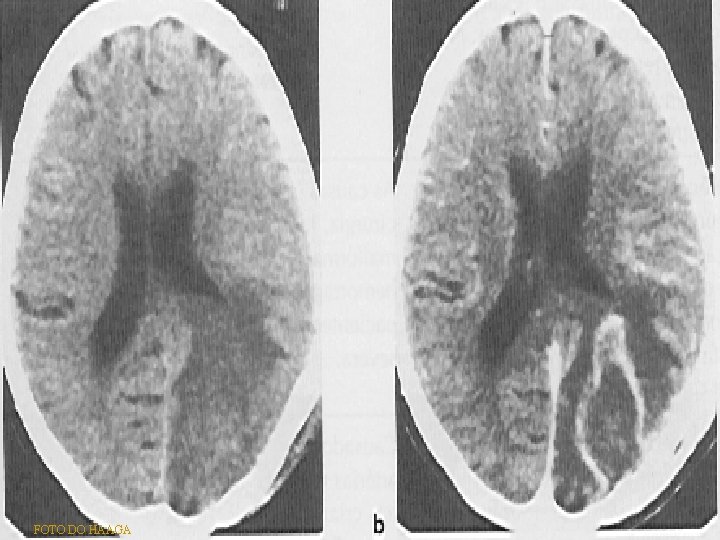

TU METASTÁTICOS • CORRESPONDEM A MANIFESTAÇÃO DE DOENÇA MALIGNA AVANÇADA • SITIOS PRIMÁRIOS MAIS COMUNS: PULMÃO > MAMA > MELANOMA > TGI/TGU • ÚNICAS OU MÚLTIPLAS (75%) • LOCALIZAM-SE HABITUALMENTE NA JUNÇÃO CINZENTA-BRANCA • SÃO OS TU INTRA-AXIAIS MAIS COMUNS, LOCALIZADOS NA F. POST. ( ADULTOS) • ENTRE A 5ª E 7ª DÉCADAS DE VIDA, RARO EM CRIANÇAS • PRINCIPAIS DIAGNÓSTICOS DIFERENCIAIS: - TU PRIMÁRIOS INTRACRANIANOS - AVC ISQ E HEMORRÁGICO - ABSCESSO CEREBRAL

IMAGINOLOGIA • RX SIMPLES: LESÕES LÍTICAS ALT NA SELA TÚRCICA • TC: LESÃO NODULAR HIPER/ISODENSA ( + COMUM), SÓLIDA OU CÍSTICA COM HALO FINO HIPERDENSO PERILESIONAL. REALCE INTENSO PELO MC. • RM: LESÃO ISOINTENSA EM T 1 E T 2 COM REALCE MODERADO PELO MC

FOTO DO HAAGA